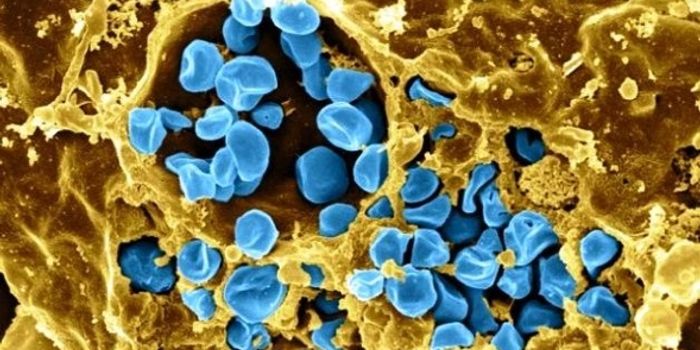

MAR 26, 2015ImmunologyAntibiotic resistance is on its way to spreading around the world among bacteria that are often involved in respiratory ...